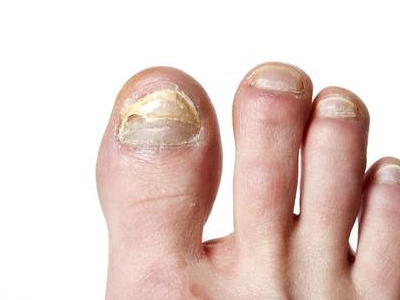

甲床炎患者受到外伤及细菌感染,可使甲床化脓及发炎,以后甲可以扭曲甚至脱落,严重患者的指(趾)头可以溃烂坏死。天疱疮、疱疹样皮炎、剥脱性皮炎、毛发红糠疹、银屑病、梅毒以及甲板下的异物都可引起甲床炎。

甲床炎患者多存在外伤史,病变一般会先从某一指甲或趾甲开始。真菌、细菌通过甲小皮侵犯甲床,继而甲床出现肿胀、化脓,且通常会伴有疼痛。

多数由于直接感染真菌、病毒引起,也可继发于天疱疮、疱疹样皮炎、剥脱性皮炎、毛发红糠疹、银屑病、梅毒以及甲板下的异物等。此外也可由甲沟炎继发而来。